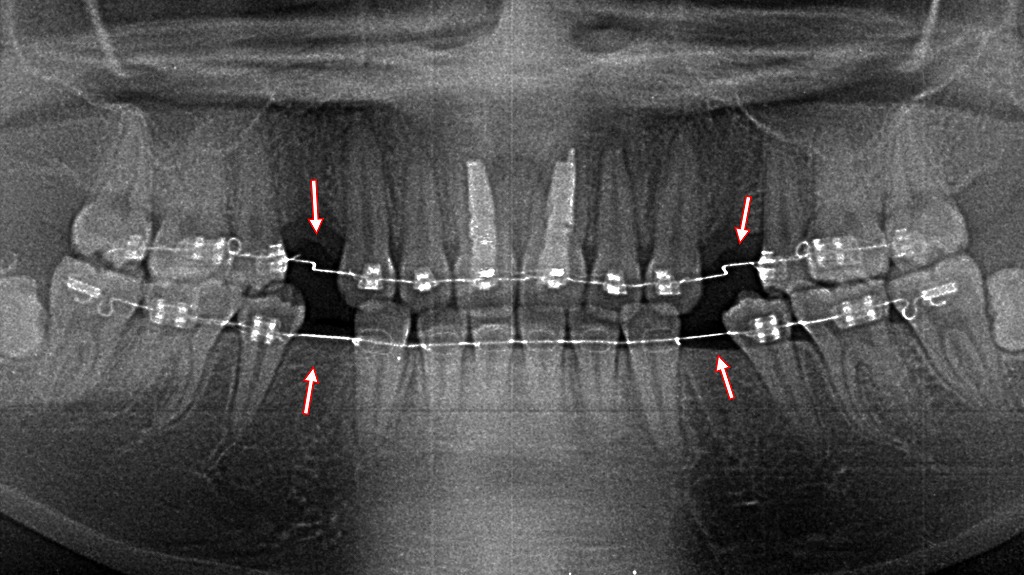

小臼歯抜歯後の矯正治療:下顎のスペース閉鎖の様子

① 下顎右4番・左5番の抜歯スペース

- **右側の第1小臼歯(4番)**と

- **左側の第2小臼歯(5番)が

矯正治療のスペース確保目的で抜歯されている状態です。

そのため、左右ともに小臼歯部に隙間(スペース)**が見られます。

② マルチブラケット装置(ワイヤー矯正)

- 上下にブラケットが装着され、アーチワイヤーが通されている標準的なワイヤー矯正の状態です。

③ パワーチェーンの装着

- 抜歯したスペースを閉じるために、

**ブラケット間にゴム(パワーチェーン)**が装着されています。 - パワーチェーンは持続的な牽引力をかけ、歯を動かして隙間を閉じる目的で使用されます。